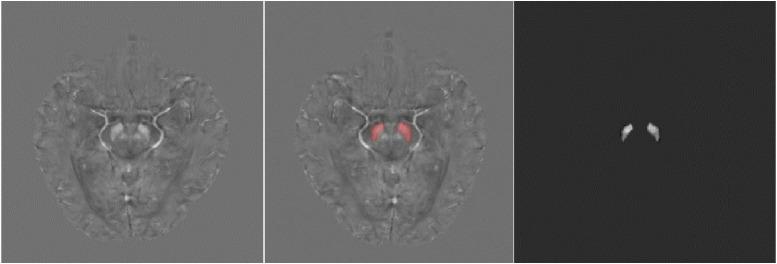

基于定量磁化率映射的混合特征提取用于帕金森病的诊断。

Quantitative susceptibility mapping based hybrid feature extraction for diagnosis of Parkinson's disease.

Parkinson's disease is the second most common neurodegenerative disease in the elderly after Alzheimer's disease. The aetiology and pathogenesis of Parkinson's disease (PD) are still unclear, but the loss of dopaminergic cells and the excessive iron deposition in the substantia nigra (SN) are associated with the pathophysiology. As an imaging technique that can quantitatively reflect the amount of iron deposition, Quantitative Susceptibility Mapping (QSM) has been shown to be a promising modality for the diagnosis of PD. In the present work, we propose a hybrid feature extraction method for PD diagnosis using QSM images. First, we extract radiomics features from the SN using QSM and employ machine learning algorithms to classify PD and normal controls (NC). This approach allows us to investigate which features are most vulnerable to the effects of the disease. Along with this approach, we propose a Convolutional Neural Network (CNN) based method which can extract different features from the QSM image to further support the diagnosis of PD. Finally, we combine these two types of features and we find that the radiomics features and CNN features are complementary to each other, which helps further improve the classification (diagnostic) performance. We conclude that: (1) radiomics features from QSM data have significant clinical value for the diagnosis of PD; (2) CNN features are also useful in the diagnosis of PD; and (3) the combination of radiomics features and CNN features can enhance the diagnostic accuracy.

帕金森病是仅次于阿尔茨海默病的老年人第二常见的神经退行性疾病。帕金森病(PD)的病因和发病机制尚不清楚,但黑质(SN)中多巴胺能细胞的丧失和过量的铁沉积与病理生理学有关。作为一种可以定量反映铁沉积量的成像技术,定量磁敏感图(QSM)已被证明是诊断 PD 的一种很有前途的方法。在本工作中,我们提出了一种使用 QSM 图像进行 PD 诊断的混合特征提取方法。首先,我们从 SN 中提取 QSM 图像的放射组学特征,并使用机器学习算法对 PD 和正常对照(NC)进行分类。这种方法可以让我们研究哪些特征对疾病的影响最敏感。除了这种方法,我们还提出了一种基于卷积神经网络(CNN)的方法,该方法可以从 QSM 图像中提取不同的特征,以进一步支持 PD 的诊断。最后,我们将这两种类型的特征结合起来,发现放射组学特征和 CNN 特征是互补的,这有助于进一步提高分类(诊断)性能。我们得出结论:(1)来自 QSM 数据的放射组学特征对 PD 的诊断具有重要的临床价值;(2)CNN 特征在 PD 诊断中也很有用;(3)放射组学特征和 CNN 特征的结合可以提高诊断准确性。